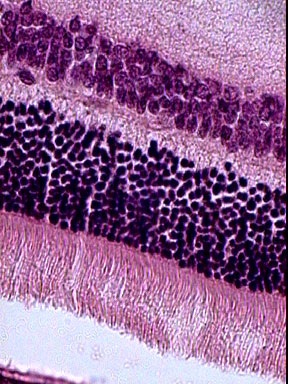

| préparation microscopique scannée | deux agrandissements : haut, bas |

cellules ganglionnaires

cellules bipolaires

photorécepteurs cellules pigmentaires |